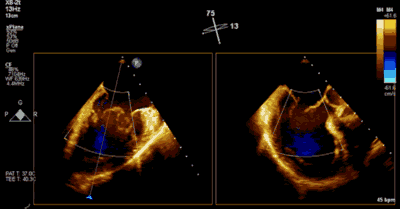

患者为73岁老年男性,既往合并冠心病、持续性心房颤动、肾功能不全病史,此次主诉“反复胸闷气促3月余”入院。诊断:心脏瓣膜病 二尖瓣脱垂伴重度关闭不全 心功能Ⅲ级(NYHA分级)。术前经胸超声心动图示:左房扩大,二尖瓣前后叶冗长、P2脱垂合并重度反流(Type II类 DMR/MR4+)。心脏测值:LA 54 x 58mm,LVD 60mm,EF% 60%,PASP 36mmHg。经食管超声心动图示:二尖瓣环左右径38mm,反流束缩流颈宽度为8.5mm,EROA 0.72cm2(PISA),舒张期二尖瓣口平均跨瓣压差2mmHg。

▲ 术前超声检查显示重度二尖瓣反流

▲ 术后超声检查显示轻度二尖瓣反流